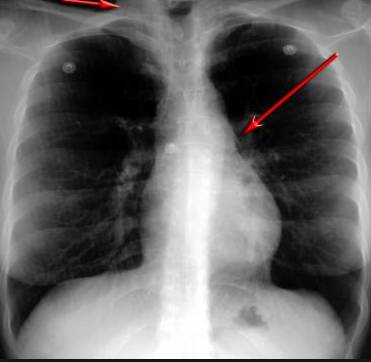

這臺機器看上去又大又笨重,

它是全世界第一臺4D醫(yī)學(xué)掃描儀

這臺4D掃描儀

能讓醫(yī)生有一雙可以透視的眼睛

整個肺部看得清清楚楚!

4D高清透視!

使用這臺掃描儀,將直接把器官變成3D圖形!細微的毛細血管,幾毫米大的肺泡和支氣管,都將能看的一清二楚!

你的每一個氣泡,每一段支氣管,哪兒有病變都清清楚楚的將展示在醫(yī)生面前!

不只是圖形,還是動態(tài)的!

這臺儀器不僅僅是一臺能拯救幾百萬條生命的高清掃描儀,它更是一場開天辟地的技術(shù)革新!因為它不僅能幫醫(yī)生看到肺病的結(jié)構(gòu)圖,

還能看到器官是如何運動的!

空氣是如何進入到肺部,氧氣是如何到血液,任何微小的變化都將曝露在醫(yī)生面前!更清晰的圖像,更細節(jié)的變化!

更短的時間,更少的輻射!

不同于CT掃描,需要從同一角度,拍下無數(shù)張器官二維圖,從而搭建3D器官結(jié)構(gòu)圖那般費時費力。

4D掃描儀將直接從不同角度,同時對人體器官進行掃描,然后通過計算機算法進行快速成像。CT需要花幾小時才能完成的工作,

4D掃描將在幾秒內(nèi)完成!

當大家還在為B超、X光、CT哪個輻射更少而爭論不休時,這臺新機器已經(jīng)比現(xiàn)有掃描儀少20%的輻射

不需要重復(fù)拍片,輻射也更少!